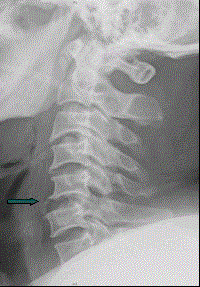

患者男,38岁,车祸伤后导致颈部疼痛、四肢瘫痪,排尿、粪失禁,ASIA分级C级,入院时间为伤后6 h,佩戴颈托入院。于急诊行颈椎正侧位X线片(如图)。...

问题 患者男,38岁,车祸伤后导致颈部疼痛、四肢瘫痪,排尿、粪失禁,ASIA分级C级,入院时间为伤后6 h,佩戴颈托入院。于急诊行颈椎正侧位X线片(如图)。 根据所学的SLIC评分,此患者评分应为(提示 此患者的MRI检查及CT检查如下图。)

选项 A、8分 B、6分 C、7分 D、4分 E、5分 F、3分

答案 A